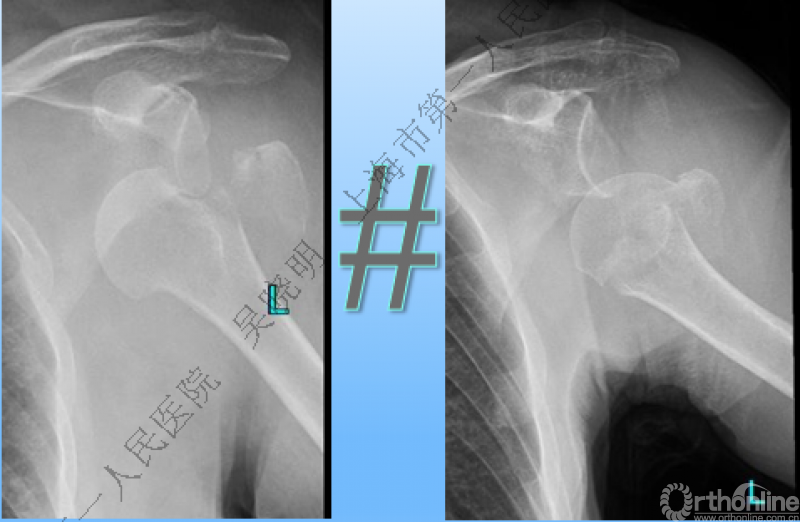

下图考虑为孤立性的大结节骨折?

看完片子,你会发现高质量的平片甚至3D CT也难以发现

肩关节前脱位伴大结节骨折:颈干角正常

无肱骨头外翻伴大结节骨折的老年性肩关节前脱位

Neer 分型:二部分大结节骨折脱位:手法复位